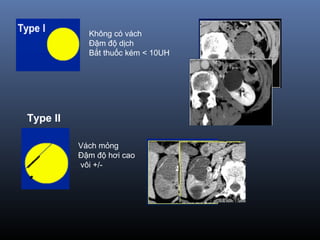

Phân lo i BosniakạType I Nang đ n thu nơ ầ :

Đ m đ d ch(-10-20 UH), đ ng d ng,gh rõ, không th y v ,không b tậ ộ ị ồ ạ ấ ỏ ắ

thu c c n quangố ả

=> Lành tính, không c n theo dõiầ

Type II Nang không đi n hìnhể :

vài vách m ng, vài đ m vôi v , đ m đ d ch cao(> 50UH)ỏ ố ở ỏ ậ ộ ị

Không b t thu c c n quang (<10UH)ắ ố ả

=> Lành tính , không c n theo dõiầ

Không có vách

Bắt thuốc kém < 10UH

Đậm độ dịch

Type II

Vách mỏng

Đậm độ hơi cao

vôi +/-